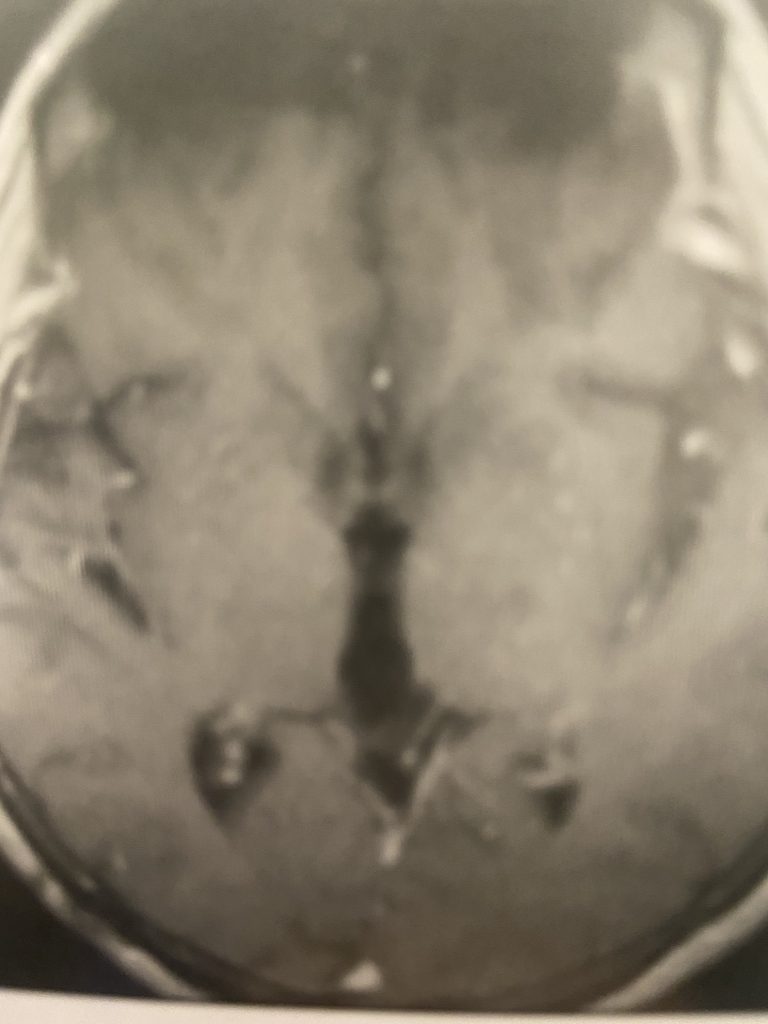

This is a 57-year-old woman with new onset memory problems and gait difficulty. MRI demonstrated a 3 cm tumor in the pineal region, most consistent with a meningioma growing inferiorly off the right tentorium.

Figure 1: Preop post contrast axial MRIs demonstrating a pineal region meningioma with hydrocephalus.

The tumor was causing compression of the upper brainstem and hydrocephalus. The tumor was removed by Dr. Michael Brisman using a right occipital / transtentorial approach.

This tumor seemed most likely to be a meningioma, given its regular shape, homogeneous enhancement pattern, and attachment to the tentorium.